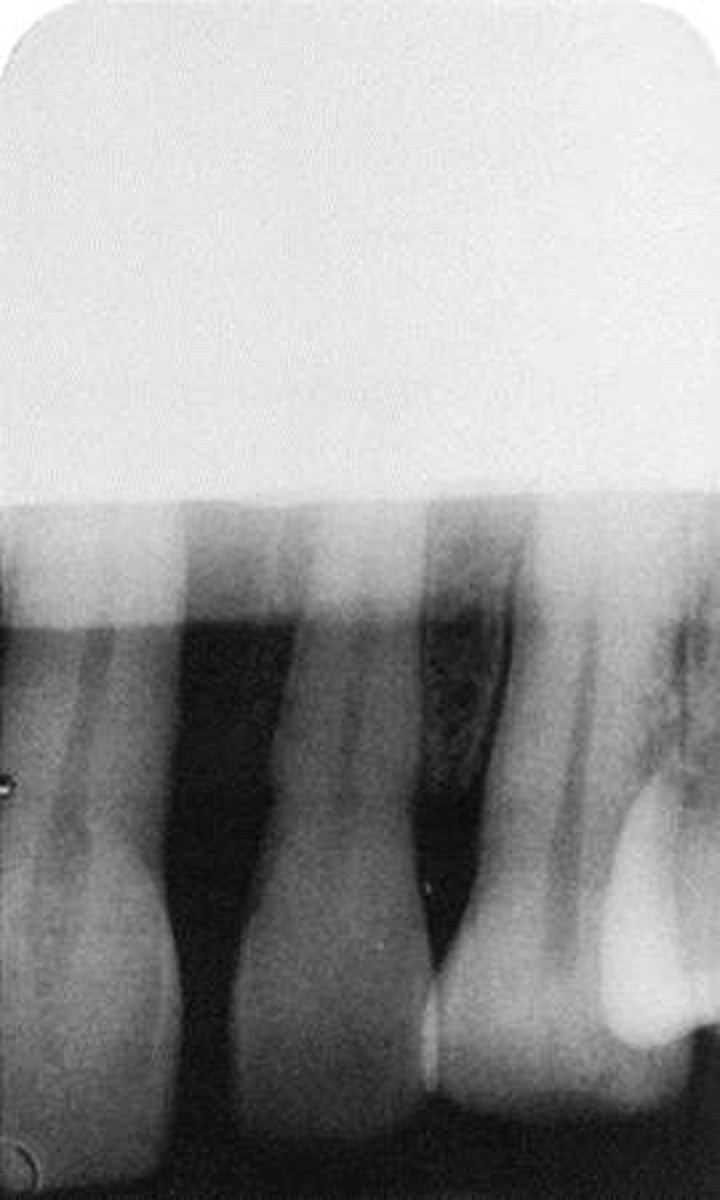

Incorrect Vertical Angulation-->Foreshortened Images

-Teeth appear short with blunted roots

-Vertical angulation was excessive, or too steep, resulting in images that are shorter than the actual teeth

-This occurs more often with the bisecting technique

-To prevent do not use excessive vertical angulation

Tube Head & PID-->Foreshortening of the image

-Excessive angulation (too steep) causing shortening of the anatomy of the teeth and/or cutting off occlusal or incisal edge.

Tube Head & PID

1. PID Too steep Vertical angulation

2. Foreshortening of the image: Excessive angulation (Too Steep)

Foreshortened image; Vertical angulation is too steep, Possible deflected film.